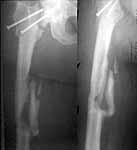

A subtrochanteric osteotomy was performed (a bit distally), after compression the lower crew was replaced with 3 monocortical. Then retrograde reaming was performed and UFN 12 mm was inserted and locked statically (with proximal screw through the plate). The neck gap looks well compressed. Image attached. Comments are welcome.

The valgus osteotomy has improved the position of the femoral neck fracture

:-)

The blade plate is in the anterior and proximal aspect of the femoral head

:-(

What activity level is planned? Keep a close eye on the femoral head and neck. They will determine outcome, primarily.